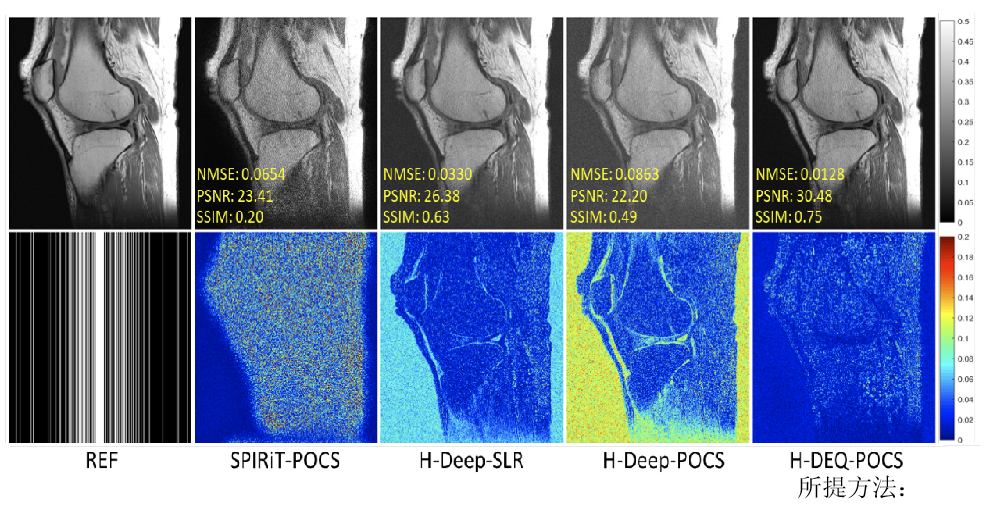

其次,针对现在主流深度学习快速重建方法可靠性不足的问题,提出了零阶算法展开网络的思想,利用网络表示正则化子零阶信息(正则化子本身),增强了网络学习的可解释性,保证了网络算法收敛性和鲁棒(正则)性。实验证明(图2),该方法重建图像质量明显优于传统方法。研究成果发表在医学成像领域著名期刊IEEETransactions on Medical Imaging

图2.测量噪声扰动下,4倍加速重建结果